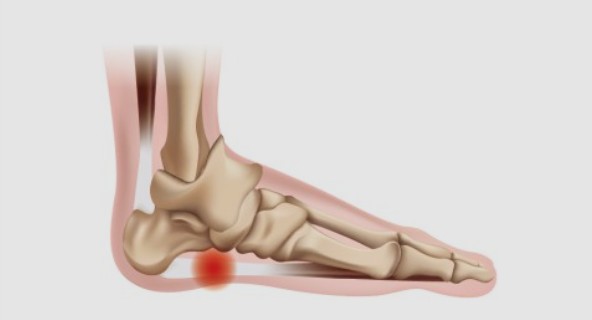

초기에는 밤에만 불편함을 느끼다가 점점 지속 시간도 늘어납니다.3. 족저근막염

발바닥 통증의 대표 질환으로,

발뒤꿈치에서 발바닥 전체로 이어지는 근막에 염증이 생기며

걷거나 서 있을 때 발바닥이 뜨겁고 찌릿한 통증을 유발합니다.

특히 아침에 첫 발을 디딜 때 더 아픈 경우가 많아요.